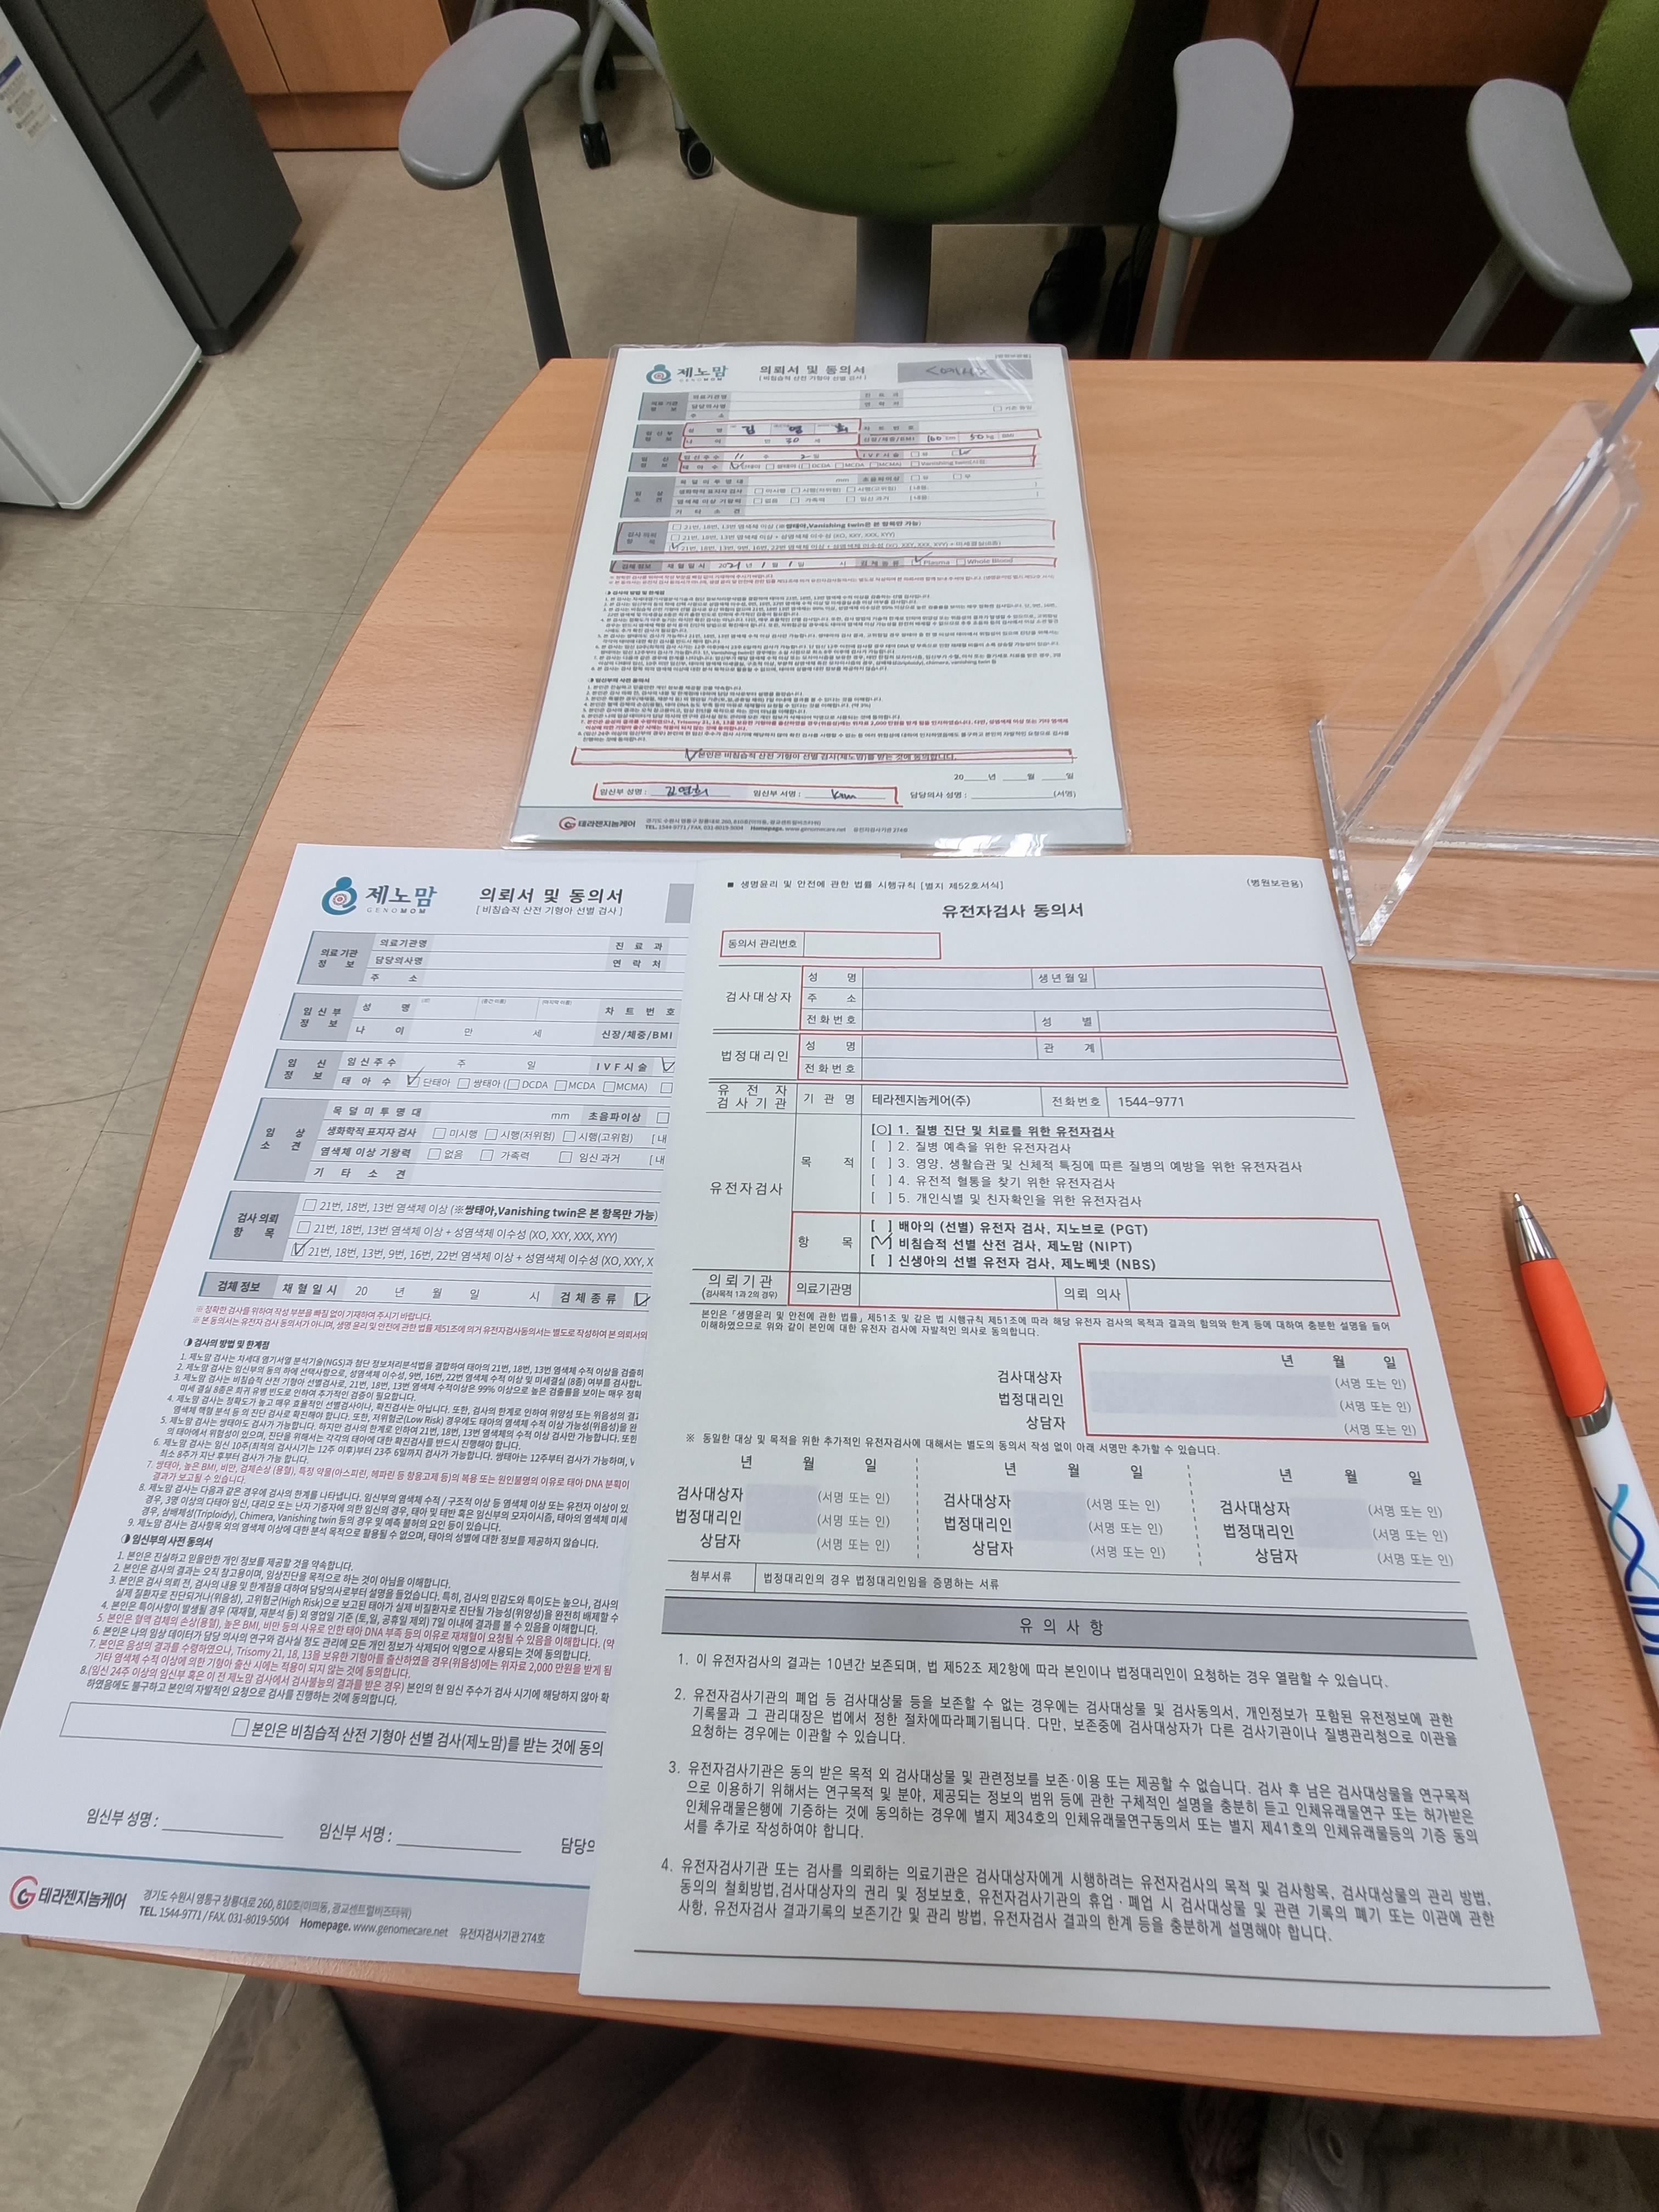

13주 니프티 검사

초음파상 이상 소견 확진

14주 니프티 결과 : 정상

BUT 초음파상 이상 소견 확진

양수검사 + 신경관결손 권고

진료) 염색체 수적이상 니프티 모두 저위험.

-> 21, 18, 13 수적이상을 총괄하는 염색체 갯수가 체크한 것. 16-17주쯤 양수+미세결실 검사 권장.

결과 2주, 4주 걸림. 16주부터 경부길이 체크.

탯줄에 낭종이 있다. 척추 휘어보이는것 확진.